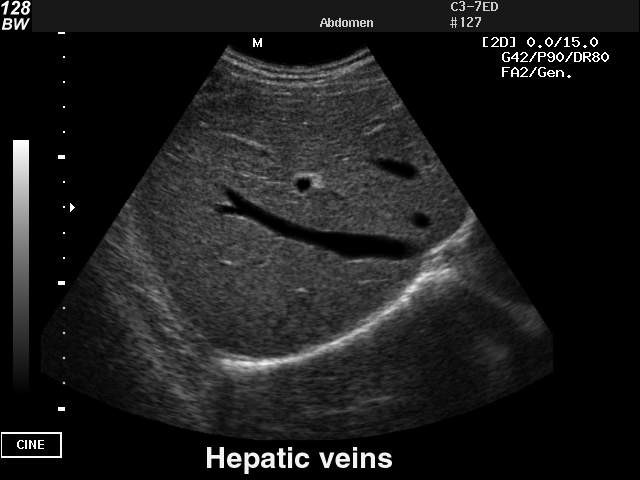

Hepatic veins, B-mode

Hepatic veins, B-mode (echogramm №26)

[RU] Ultrasound image №26: Hepatic veins in B-mode.

Echogramm was received by ultrasound scanner SonoAce-128BW (out of production).